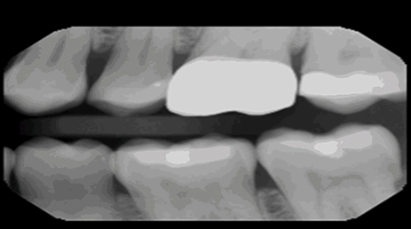

VELMENI for Dentists® 2D

VELMENI is as easy to use as it is powerful. Scan 2D radiographs to increase detection accuracy by 30%. FDA cleared for 2D Panoramic, Bitewing and Periapical X-Rays.